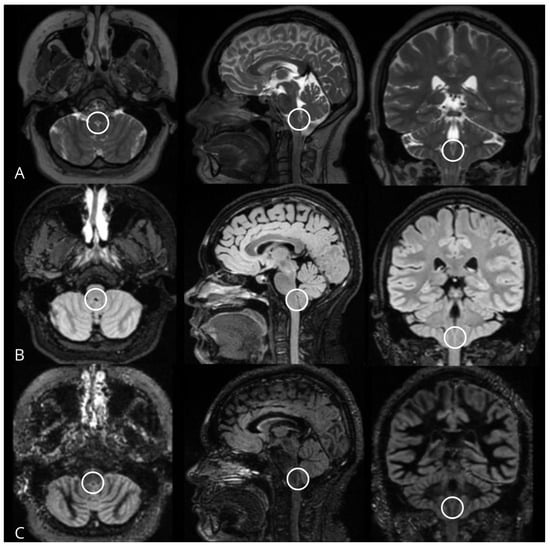

In 27.6% of the 3D FSE Cube T2WI sequence-planes, it was not possible to visualize the AP, compared to 1% in the 3D FSE Cube FLAIR sequence. In contrast, the AP was visualized in 100% of the 3D DIR sequence-planes, at least at a “possible” level of visibility. Additionally, the 3D DIR sequence showed superior performance, with a greater number of sequence-planes displaying the AP as “clearly visible”, with statistically significant differences favoring the 3D DIR sequence (p < 0.001) (Figure 2) (Table 3).

Figure 2. MRI of a patient with MS, in whom the area postrema cannot be identified in the 3D FSE Cube T2WI sequences (A) in axial and sagittal planes, but is visible in the axial and sagittal planes of 3D FSE Cube FLAIR (B) and 3D DIR (C) sequences.